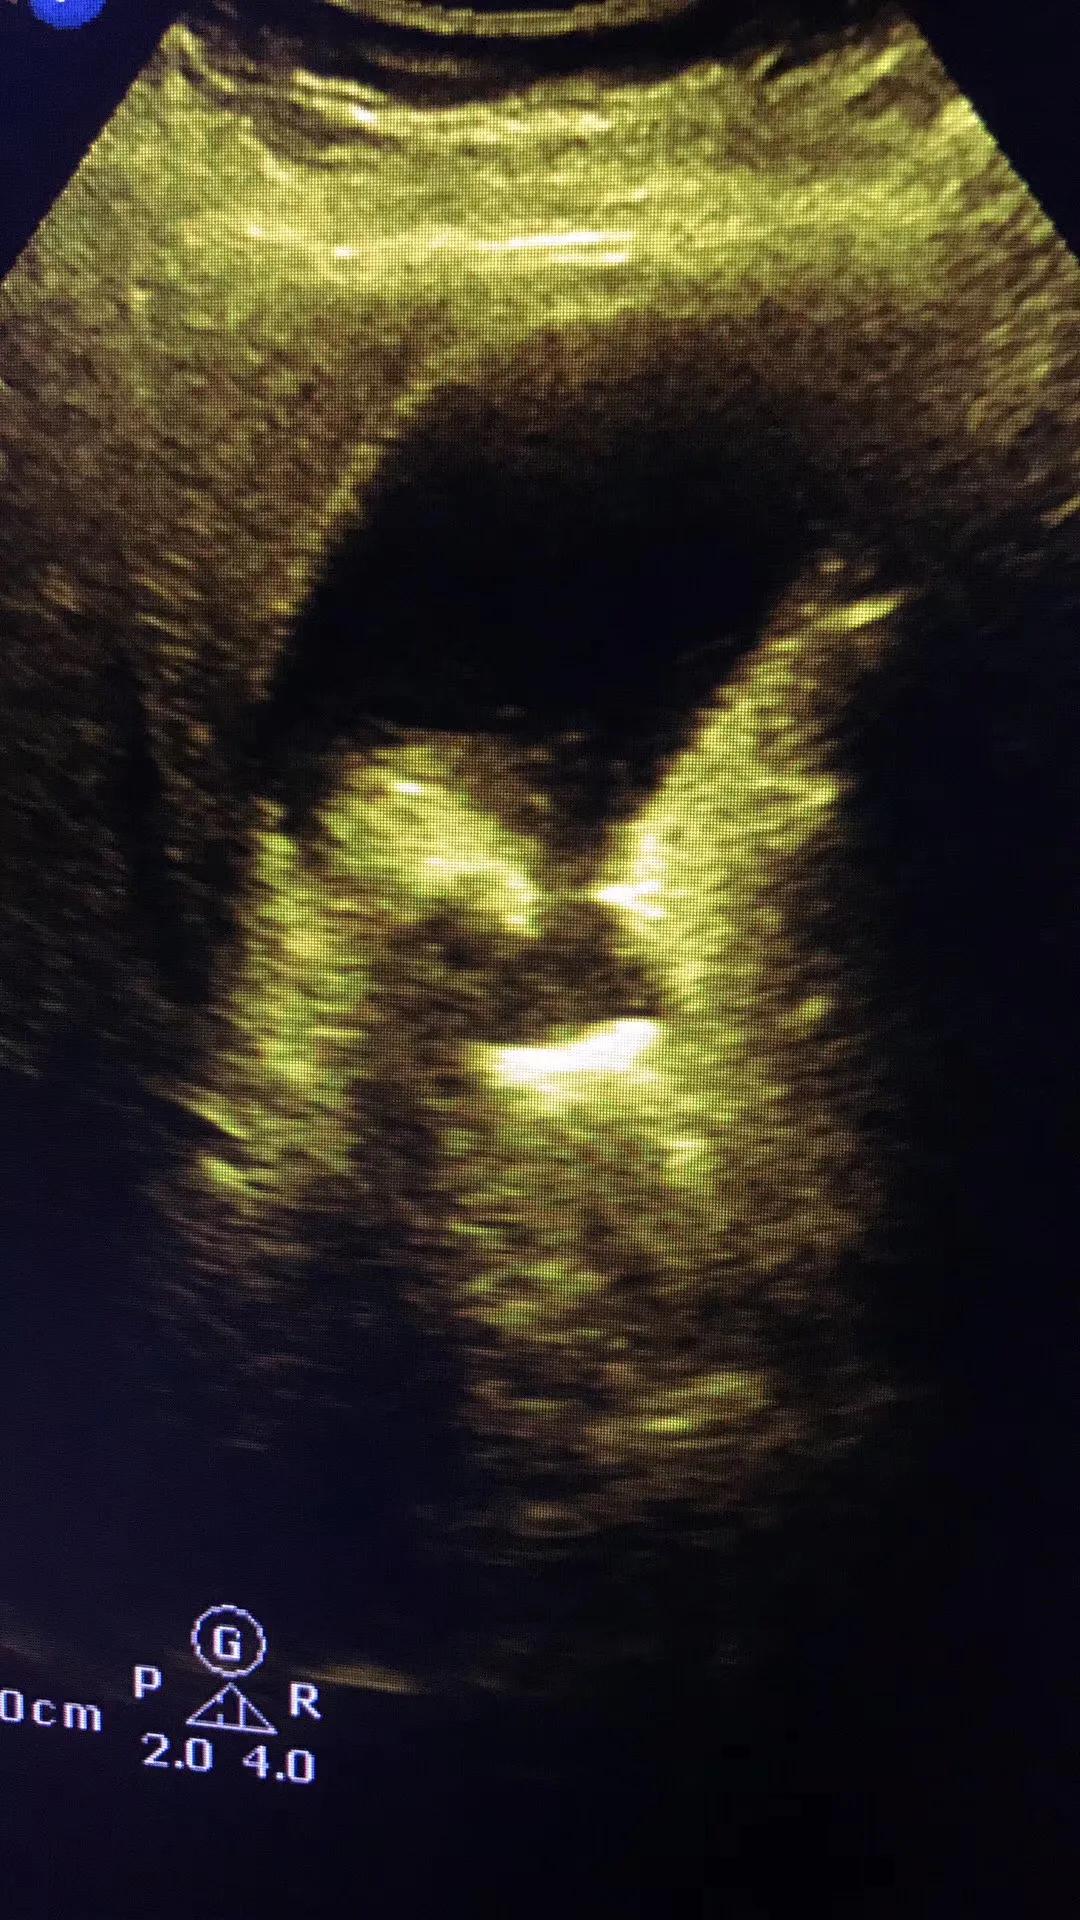

病例1.患者女性,57岁,胆囊颈部结石嵌顿继发急性胆囊炎!胆囊肿的像个茄子!